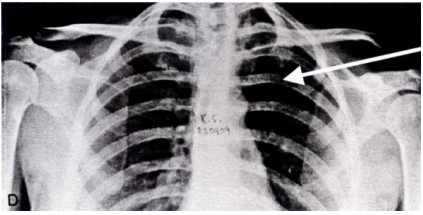

26 胸部 X 光片,箭頭所示為第幾根肋骨?

(A)三 (B)四 (C)五 (D)六